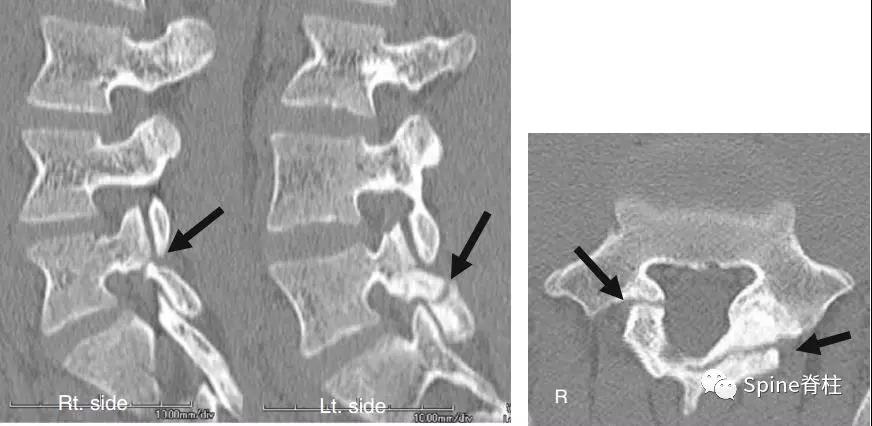

3. 峡部裂与椎弓根裂共存的典型病例

2003年发表在Am J Sports Med杂志(IF=6.20)上的病例报道,很好的阐述了峡部裂和椎弓根裂的变化。描述一个17岁的棒球运动员,运动后腰痛1月余,随访的辅助检查提示相同椎体水平出现的3个连续性应力性骨折:第一次为左侧峡部,第二次为右侧椎弓根,第三次为右侧峡部。

图:起始CT提示L5左侧峡部裂(双箭头),起始CT检查后2个月复查可见出现右侧椎弓根裂(单箭头),4个月复查可见椎弓根裂愈合(单箭头)